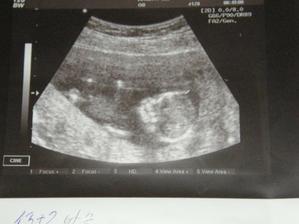

Kontrola dopadla v pořádku. Byl to nezapomentulený zážitek vidět manžela jak je štěstím bez sebe...prcek se tak kroutil, mrskal, že ho nešlo ani vyfotit, prý si s paní doktorkou pěkně vyhrál....:o)

Jinak podle ultrazvuku jsme 13+2, podle MS 12+4, takže termín porodu zůstává.